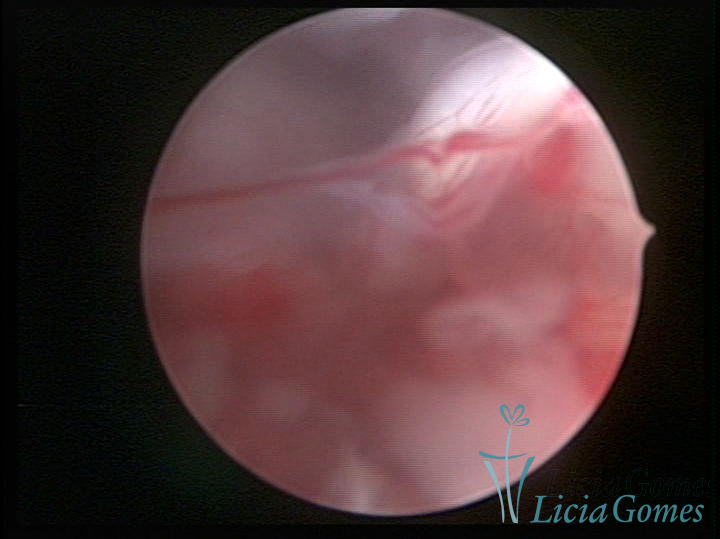

A histeroscopia permite analisar as características da superfície endometrial, não podendo avaliar a profundidade ou o grau de invasão miometrial.

Este pode apresentar uma gama variável de aspectos macroscópicos, com aspecto pseudopolipoide; lembrando tecido cerebroide ou com reação deciduoide;a vascularização superficial é mais evidente e com vasos em formatos de saca-rolha ou espirais visualizando também a vascularização com atípias, com aumento do calibre dos vasos superficiais, pode ser encontrado também tecido em necrose, poderá haver um pequenos dendritos (papilomatoso).